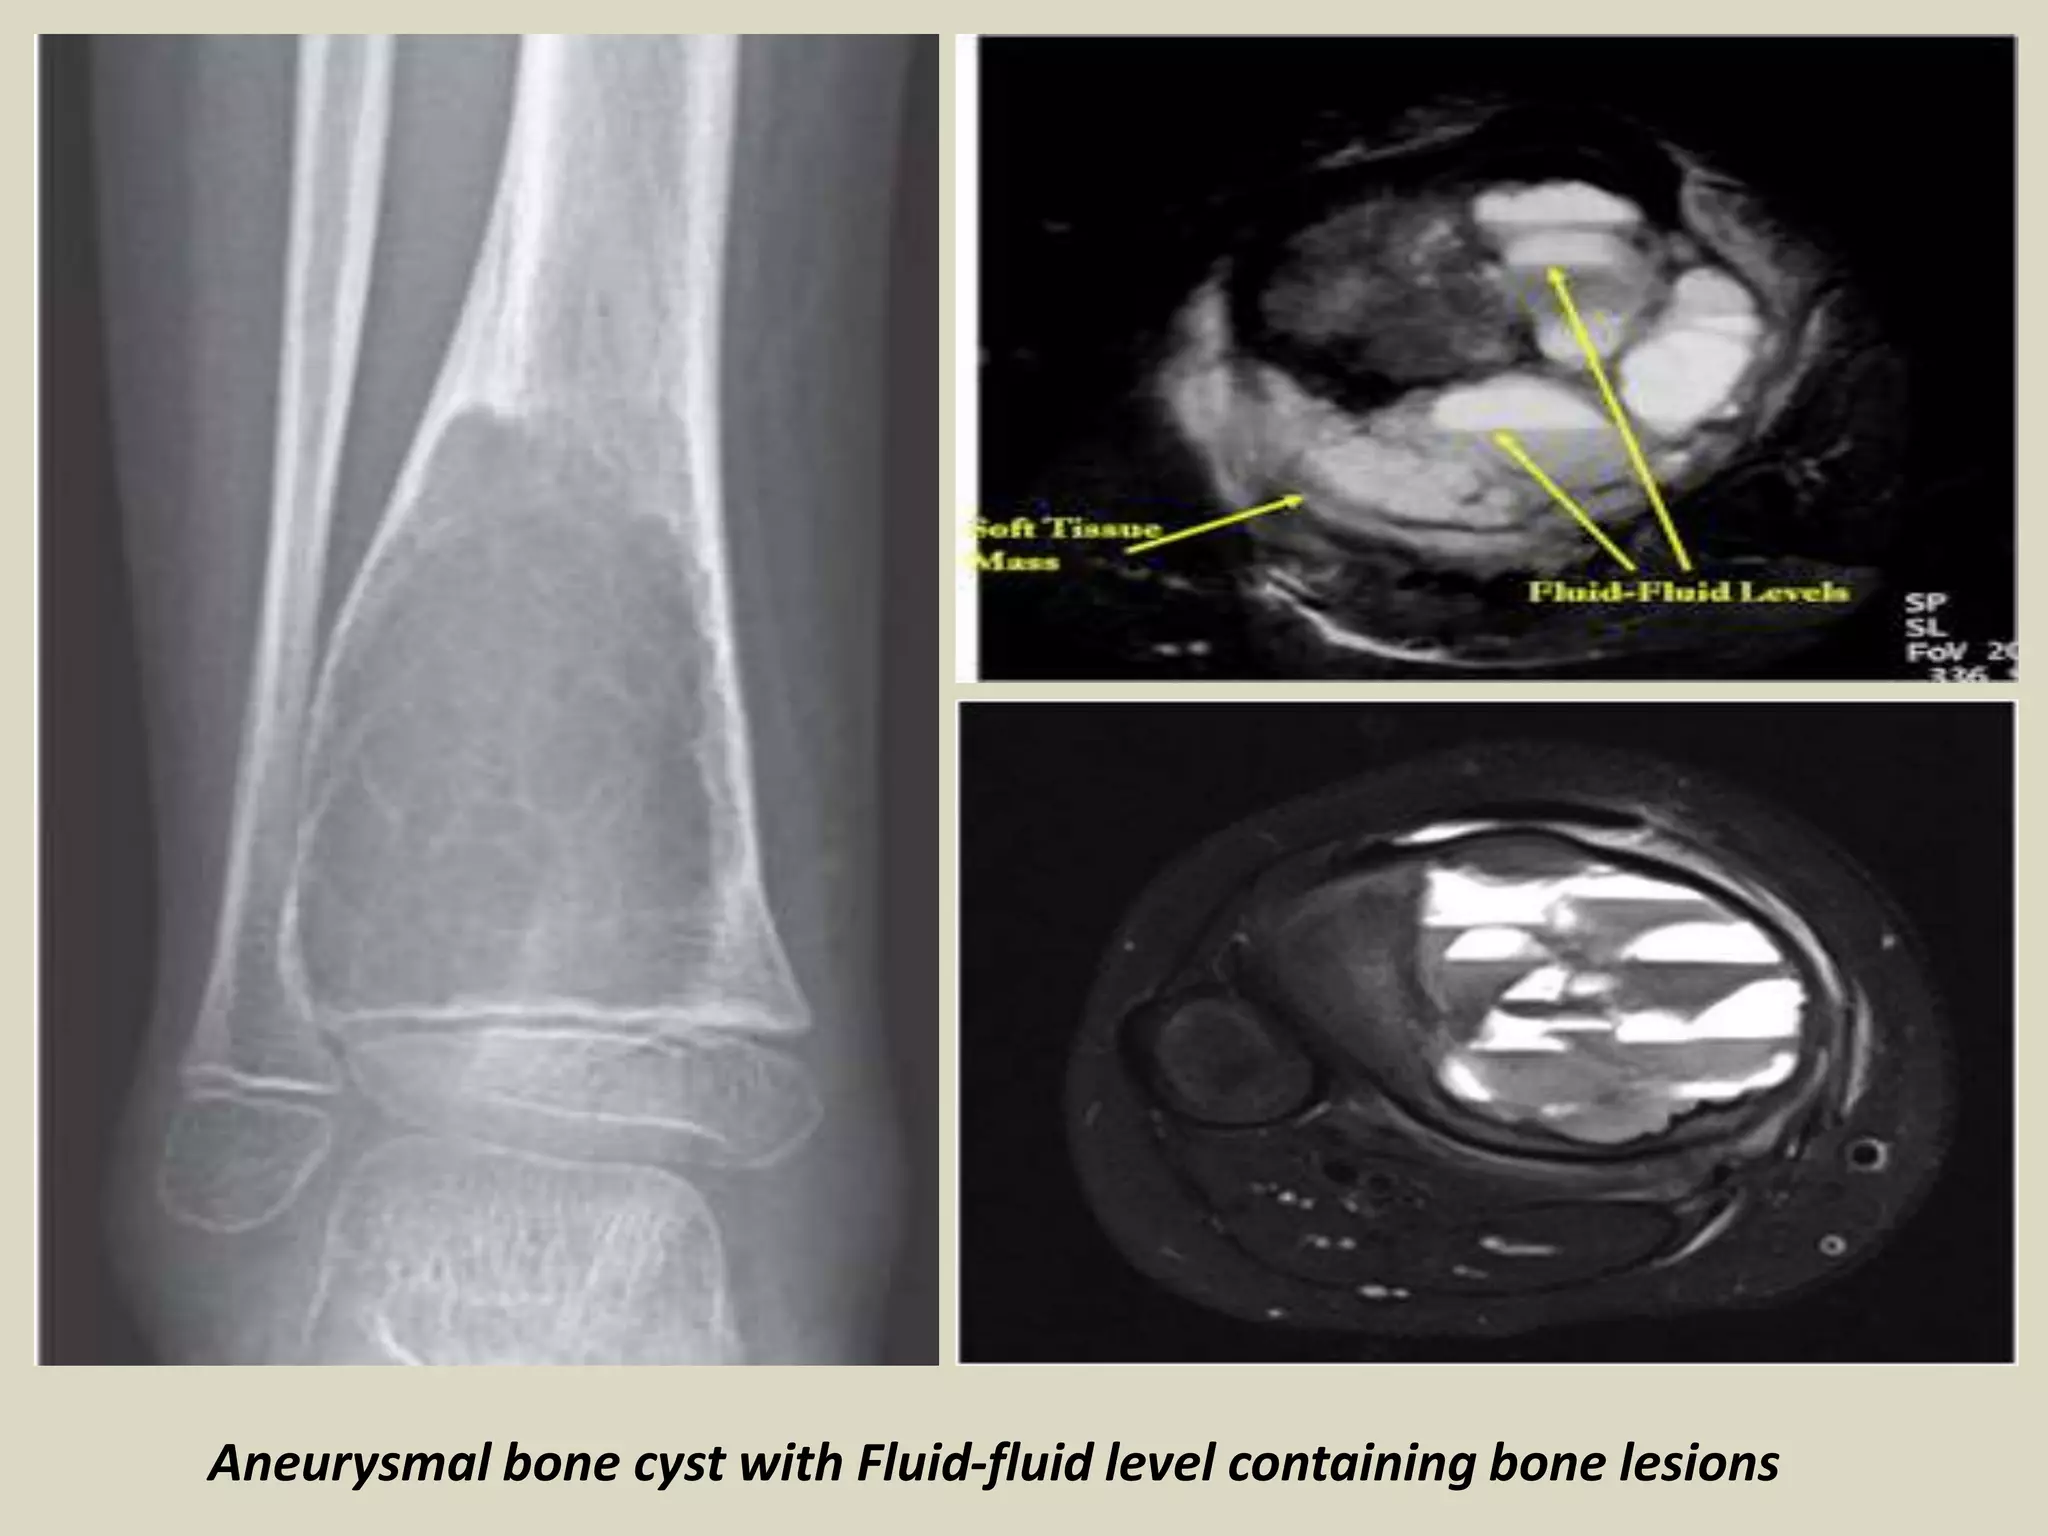

ANEURYSMAL BONE CYST (ABC).

Definition:

- Benign multiloculated , blood-filled cystic mass that is

often expansile and destructive.

Imaging:

- Usually eccentric, expansile lesion with well defined margins.

- Most lesions are completely lytic and often contain a

thin shell of reactive bone at the periphery.

- CT and MRI may demonstrate internal septa and

characteristic fluid-fluid level.

Aneurysmal bone cyst with Fluid-fluid level containing bone lesions

(a) Contrast CT head showing multi-loculated aneurysmal bone cyst of

(b) the occipital bone with total destruction of bone and peripheral wall .